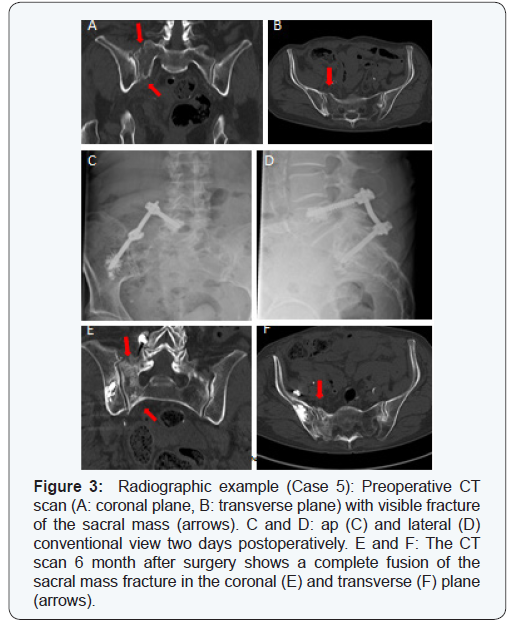

Data gathered from medical records included posttraumatic status and findings from radiographs. Assessment tools such as VAS (Visual Analogue Scale, from 0 to 10, 0 = no pain, 10 = very strong pain), the Barthel Index and Instrumental Activity of Daily Living (IADL) were used to document indicators postoperatively at 6 weeks, 3 months and 6 months (Figure 2). Conventional radiographs were done postoperatively at 6 weeks, 3 months and 6 months. To confirm complete fracture healing, an additional CT scan of the pelvis was done after 6 months (Figure 2). Additionally, factors such as the delay to surgery, time of operation, duration of the hospital stay, complications and the need for orthopaedic hardware removal were extracted from the records.

Radiographs and medical outcomes

Final CT scans at 6 month follow up visits were done for 12 patients (2 patients died before final assessment). Complete fusion of the posterior pelvic ring was confirmed in all 12 cases (Figure 3). Eleven patients also had a ventral pelvic ring fracture, but only 4 of the fractures had to be surgically stabilised. One patient (case 12) showed a delayed union of the inferior pubic ramus and reported at the final assessment minor residual pain while in a seated position (VAS 1). In 10 patients, the ventral pelvis ring was completely fused after 6 month.

A secondary dislocation of the ventral pelvic ring occurred in one patient (case 5) 60 days after primary posterior stabilisation. The dislocation was stabilised by minimally invasive plating. Case 10 had an open book fracture and was operated at two stages during the same hospital stay. There was no wound healing disorders or deep wound infection in any patients.